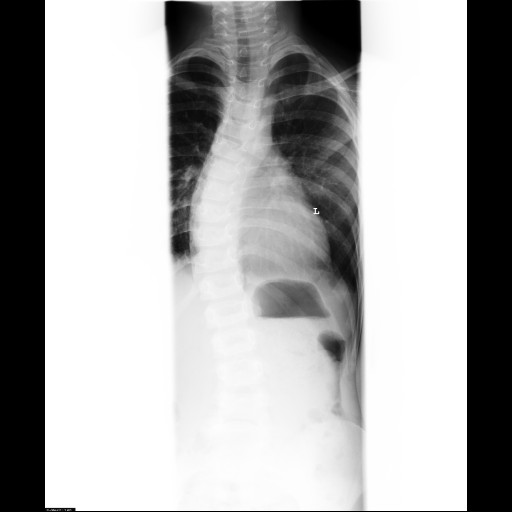

herr rahmouni sagte, er wollte die hws sehen - am besten bis zum beckenkamm - aber ich finde, man erkennt so gut wie nix im unteren bereich :(

toll - jetzt hab ich mir die "alten" und die "neuen" bilder mal angesehen ... meiner meinung nach, hat sich die skoliose ordentlich verschlechtert - findet ihr das im direkten vergleich auch? *bildanhäng*

ob das Röntgen ausreichend ist, kann ich dir leider nicht sagen. Ich glaube, das Becken auf dem Bild ist wichtig, um zu sehen, ob ein Schiefstand besteht und ob das Becken verdreht ist. Bei den Bildern von Dr. Hoffmann sieht man auch noch die Körperkonturen mit, also z.B. die herausstehende Hüfte ist da mit ersichtlich. Was bei beiden Bildern aber fehlt, ist das Gitter im Hintergrund. Daran sieht man z.B. besser, ob die Wirbelsäule im Lot steht.

meiner meinung nach, hat sich die skoliose ordentlich verschlechtert - findet ihr das im direkten vergleich auch?

Wieso wurde das neue Bild denn nicht ausgemessen? Ich glaube auch, dass es sich oben etwas verschlechtert hat, in der LWS siehts dafür etwas besser aus. Könnte also sein, dass sie einfach etwas anders stand. Aber ab Morgen gehts dann ja eh aufwärts, d.h. erstmal wirds wohl schwierig mit der Eingewöhnung, aber die Sorge der ständigen Verschlechterung ist erstmal weg :)